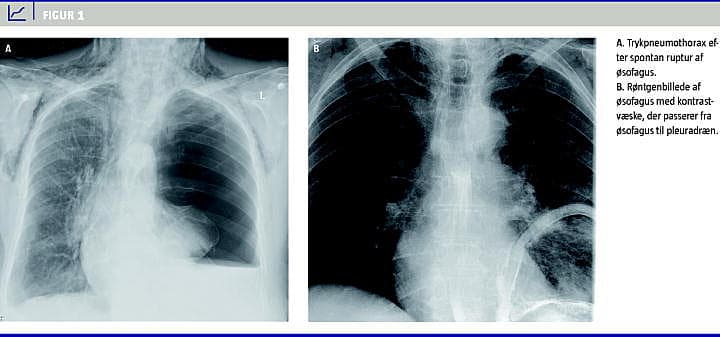

En 75-årig kvinde, der tidligere stort set havde været rask, blev indlagt akut med åndenød. Hun var ikkeryger, men havde tidligere fået diagnosticeret let astma. Ved indlæggelse havde hun dyspnø, havde hostet i en uge og havde haft smerter nedadtil på thorax' bagside ved dyb inspiration. Der havde ikke været nogen forudgående traumer eller opkastninger. Objektivt set var hun relativt upåvirket, hun var afebril, havde let hviledyspnø og en iltsaturation på 94%. Der var nedsat luftskifte bag på venstre thoraxhalvdel. En røntgenundersøgelse af thorax viste total venstresidig pneumothorax med overskydning af mediastinum mod højre, subkutant emfysem og lidt pleuravæske (Figur 1 ). Der blev straks anlagt Portexdræn 16 F i den forreste aksillærfold, og drænet fungerede med rigelig luft. Pneumothorax aftog, men pleuraansamlingen tiltog, hvorfor der blev skiftet til et tykkere dræn samt tilkoblet vandlås og sug. På mistanke om empyem og begyndende sepsis blev patienten sat i behandling med cefuroxim og metronidazol. Herefter blev der i de næste to døgn udtømt over 6 l stærkt plumret væske. Koncentrationen af C-reaktivt protein steg fra initialt 84 til 602 mg/l (referenceværdi: 0-8 mg/l). Dyrkning af pleuravæske viste vækst af tarmbakterier (bl.a. Citrobacter freundii ), hvorfor man skiftede antibiotika til piperacillin/tazobactam. Efter forbigående blodtryksfald, atrieflimren og konfusion bedredes patienten efter at have fået intravenøs væske og være blevet behandlet med digitalisglykosider. På mistanke om perforation fra mave-tarm-kanalen til pleura blev der foretaget en computertomografi af thorax suppleret med en røntgenundersøgelse af øsofagus, hvorved der blev påvist perforation af venstre side af øsofagus lige over diafragma med passage af kontrastvæske til pleuradrænet. På mistanke om Boerhaaves syndrom blev patienten overflyttet til thoraxkirurgisk afdeling. Ved overflytningen var hun relativt upåvirket og havde stabile blodværdier. Under den efterfølgende operation blev der konstateret benign ruptur af den distale øsofagus, hvorefter der blev anlagt en stent. Desuden blev der foretaget dekortikering af venstre pleura og spaltning af pleura parietale for at sikre afløb af pus fra mediastinum til pleurahulen. Efterforløbet var kompliceret, og mors indtrådte 19 dage efter primærindlæggelsen.